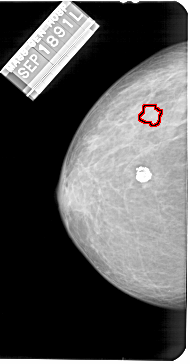

A_1568_1.LEFT_CC

LEFT_CC LINES 5446 PIXELS_PER_LINE 2836 BITS_PER_PIXEL 12 RESOLUTION 43.5 OVERLAY

FILE: A_1568_1.LEFT_CC.OVERLAY

TOTAL_ABNORMALITIES 1

ABNORMALITY 1

LESION_TYPE MASS SHAPE LOBULATED MARGINS MICROLOBULATED

ASSESSMENT 4

SUBTLETY 2

PATHOLOGY BENIGN

TOTAL_OUTLINES 1

BOUNDARY